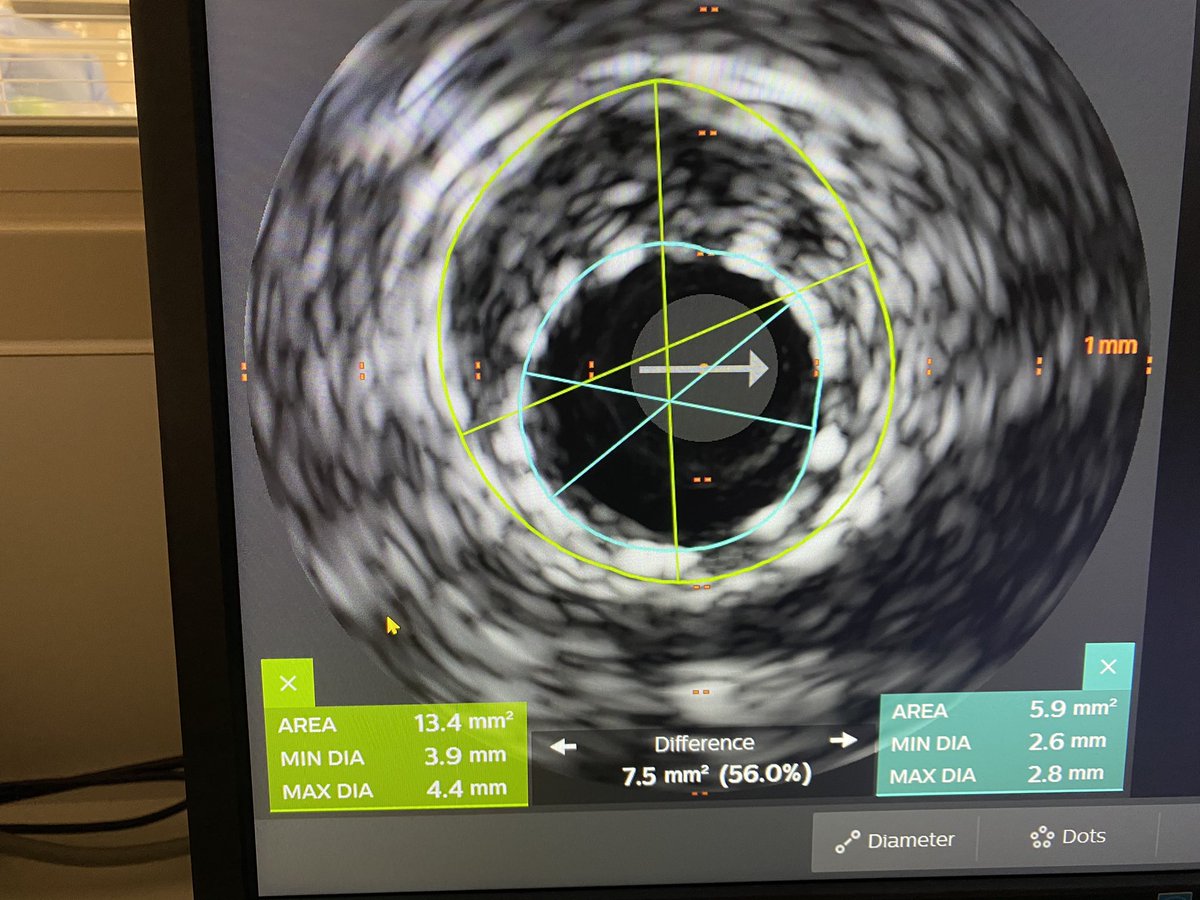

IVUS showed prior LAD 2.75mm stent in 4.25 vessel and 4.5mm in more Prox segment.

Dropped new stent 4.5mm and postdilated old stent to 4.25mm. Post IVUS with excellent expansion and no more malapposition. Looks grossly oversized on post angio.